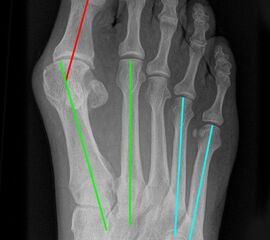

Eine Verbreiterung des Vorfußes wird als Spreizfuß bezeichnet. Ursächlich ist meist eine Deviation des ersten Metatarsale nach medial und/oder eine Abweichung des fünften Metatarsale nach lateral. Die Abweichung kann im Röntgenbild quantifiziert werden. Der Winkel zwischen Os metatarsale I und II wird als pathologisch zu bezeichnet, wenn er in der belasteten dorsoplantaren Röntgenaufnahme 9° überscheitet. Der Intermetatarsalwinkel IV/V wird ab einem Wert von mehr als 8° als erhöht.

Abbildung 16: Belastetes dorsoplantares Röntgenbild des Fußes. Zur Beurteilung des Spreizfußes wird der Intermetatarsalwinkel I/II (grüne Linien - Norm < 9 Grad) und der Intermetatarsalwinkel IV/V (blaue Linien - Norm < 8°) bestimmt. Die Abweichung der Großzehe ist durch den Hallux valgus Winkel definiert (grüne/rote Linie), eine Fehlstellung innerhalb der Großzehe durch den Interphalangealwinkel (rote/gelbe Linie) (M. Walther).